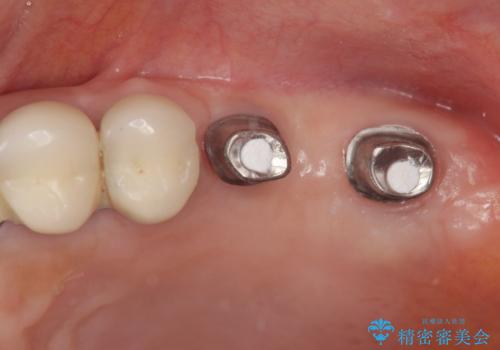

遊離端ブリッジ インプラント補綴への設計変更

支台となる小臼歯に過大な負担のかかる遊離端ブリッジが装着されていたため、義歯かインプラントを用いた再補綴計画を提案しよりしっかりと噛めるインプラント治療をご希望されました。

力学的に無理のある遊離端ブリッジをインプラントを用いて長期的な予後を見込める補綴状態へと改善しました。